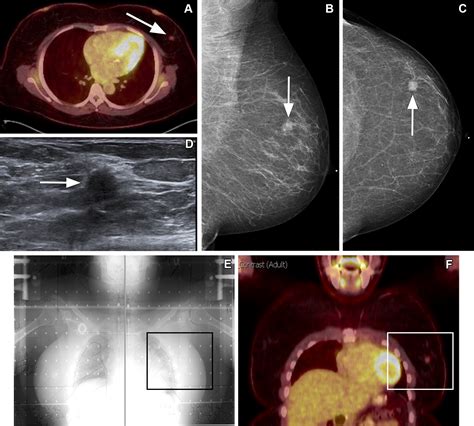

Modern imaging, such as PET-CT scans and MRIs, is the primary reason why we can be so specific about identifying Cancer At Rt. These technologies provide high-resolution images that allow radiologists to pinpoint the exact coordinates of a malignancy. When you review your scan results, look for these markers:

• Coordinates: Precise measurements of the mass's position within the organ.

• Involvement of Adjacent Structures: Whether the cancer has extended beyond the right-side boundary.

• Lymph Node Status: Often, clinicians look at the right axillary (for breast) or right hilar (for lung) lymph nodes to see if the condition has spread locally.